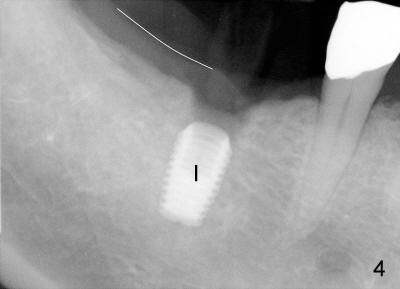

In case that there is an oral infection, submerged implant (Fig.4: I; Bicon 5x8; white line indicates gingival margin) may reduce the chance of pathogen contamination postoperatively. Fig.5 shows slight wound gaping after suture removal, one week postoperatively. In contrast, the implant in Fig.4' (Tatum 6x17) is non-submerged (white line indicates gingival margin). Two week post-operatively, an infection develops buccal to the implant (Fig.5'). Bone loses around the non-submerged implant 1 month after placement (Fig.4"). Finally the implant has to be removed. Return How to Avoid Post-implant Infection